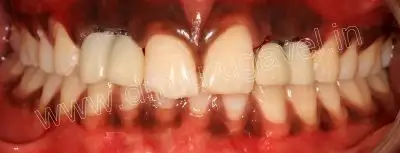

- pmma crown fixed in relation to 12,13,22,23 region

post-op front view

- Advised patient to come after 4-6 months of healing period for permanent zirconia crown